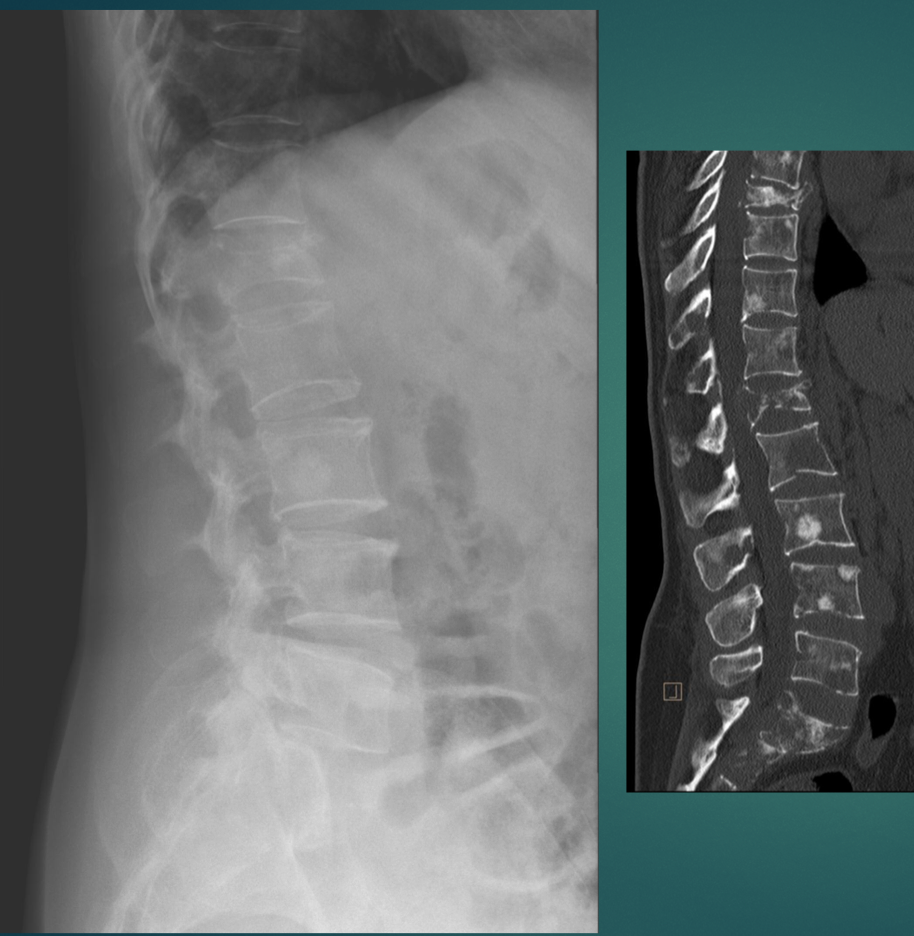

55 YO M Low back pain, insidious onset. Decrease in appetite for the last several months.

Multiple, punched out, osteolytic lesions

think: MM or mets